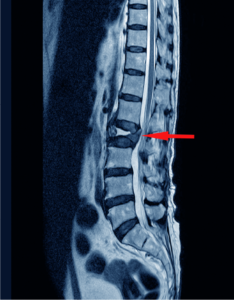

Lumbar Disc Herniation

Lumbar disc herniation is the most common cause of low back pain and leg pain (sciatica). The lumbar intervertebral discs are flat and round.